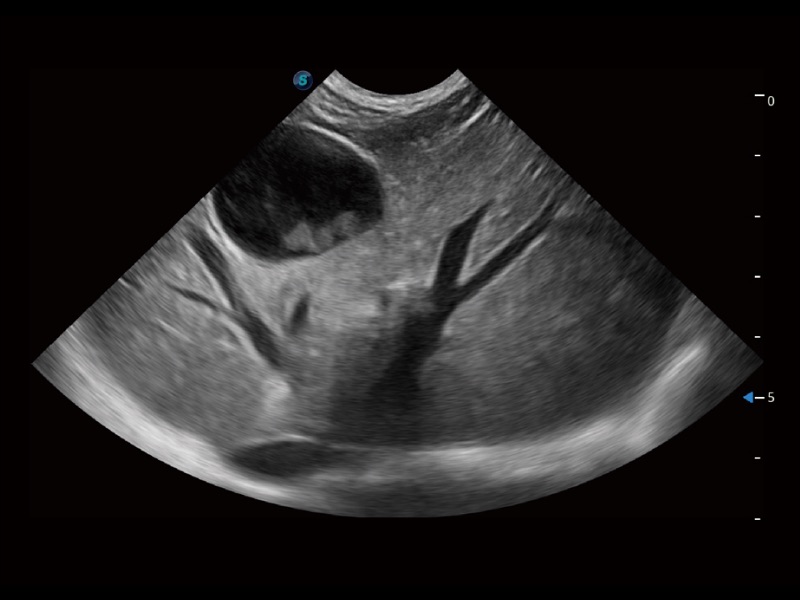

通过色彩血流和实时宽景相结合,可观察到完整的静脉或动脉的血流,方便医生检查。实时扫查过程中,如有任何操作失误也可以很容易地进行回扫擦除,而不会中断扫查。

为精细结构及组织边缘提供高清晰度的图像和更大的成像视野。帮助减轻医生的用眼疲劳,快速精准获得测量的数据。